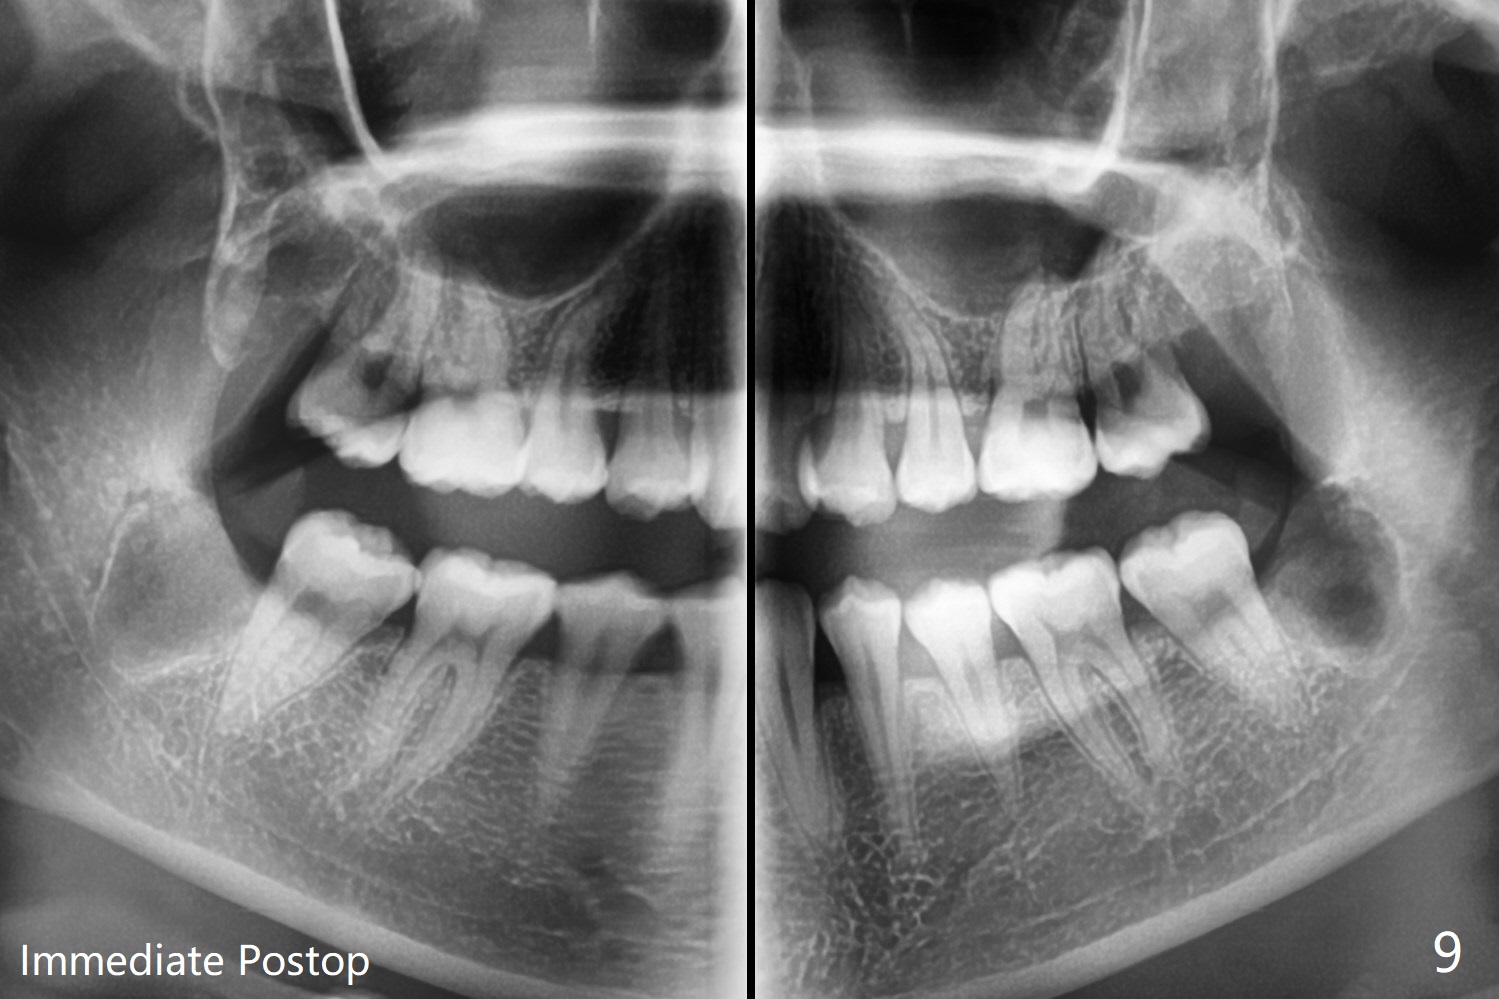

19岁女想在上大学前一次性拔除四个智齿(图一),术前口角涂抗病毒药粉(Acyclovir)凡士林(图二)。图三显示右上磨牙区,L型切口将做在第二磨牙远中(图四),光注射上牙槽后神经止痛还不够,第二磨牙上方还必须使用利多卡因(含肾上腺素1:50,000,而不是1:100,000,止血效果好)。上颌智齿区骨质松软,不必用手机钻头切骨产生purchase point,可以使用Crane Pick插入智齿近中(图五)慢慢撬动牙齿,防止大块上颌结节骨折。如果觉得杠杆作用不够,使用Potts(图六)让牙齿脱位。图七显示右下智齿区,由于舌神经位于牙槽嵴舌侧粘膜下,切口不要超过牙槽嵴(图八)。图九显示术后即刻,下颌智齿牙槽窝密度不同。原来右下牙槽窝放置骨胶原塞,而左下胶原塞。